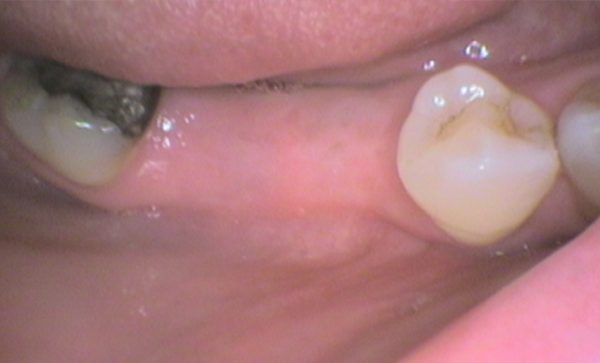

Case 10